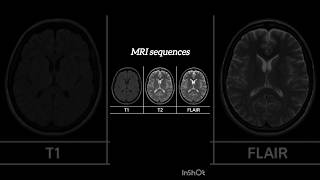

0:09

Mri sequences#shorts #radiography #shortsfeed #mri #mriscan #mrincredible

Vidisha Singh

Shared 6 months ago

1.2K views